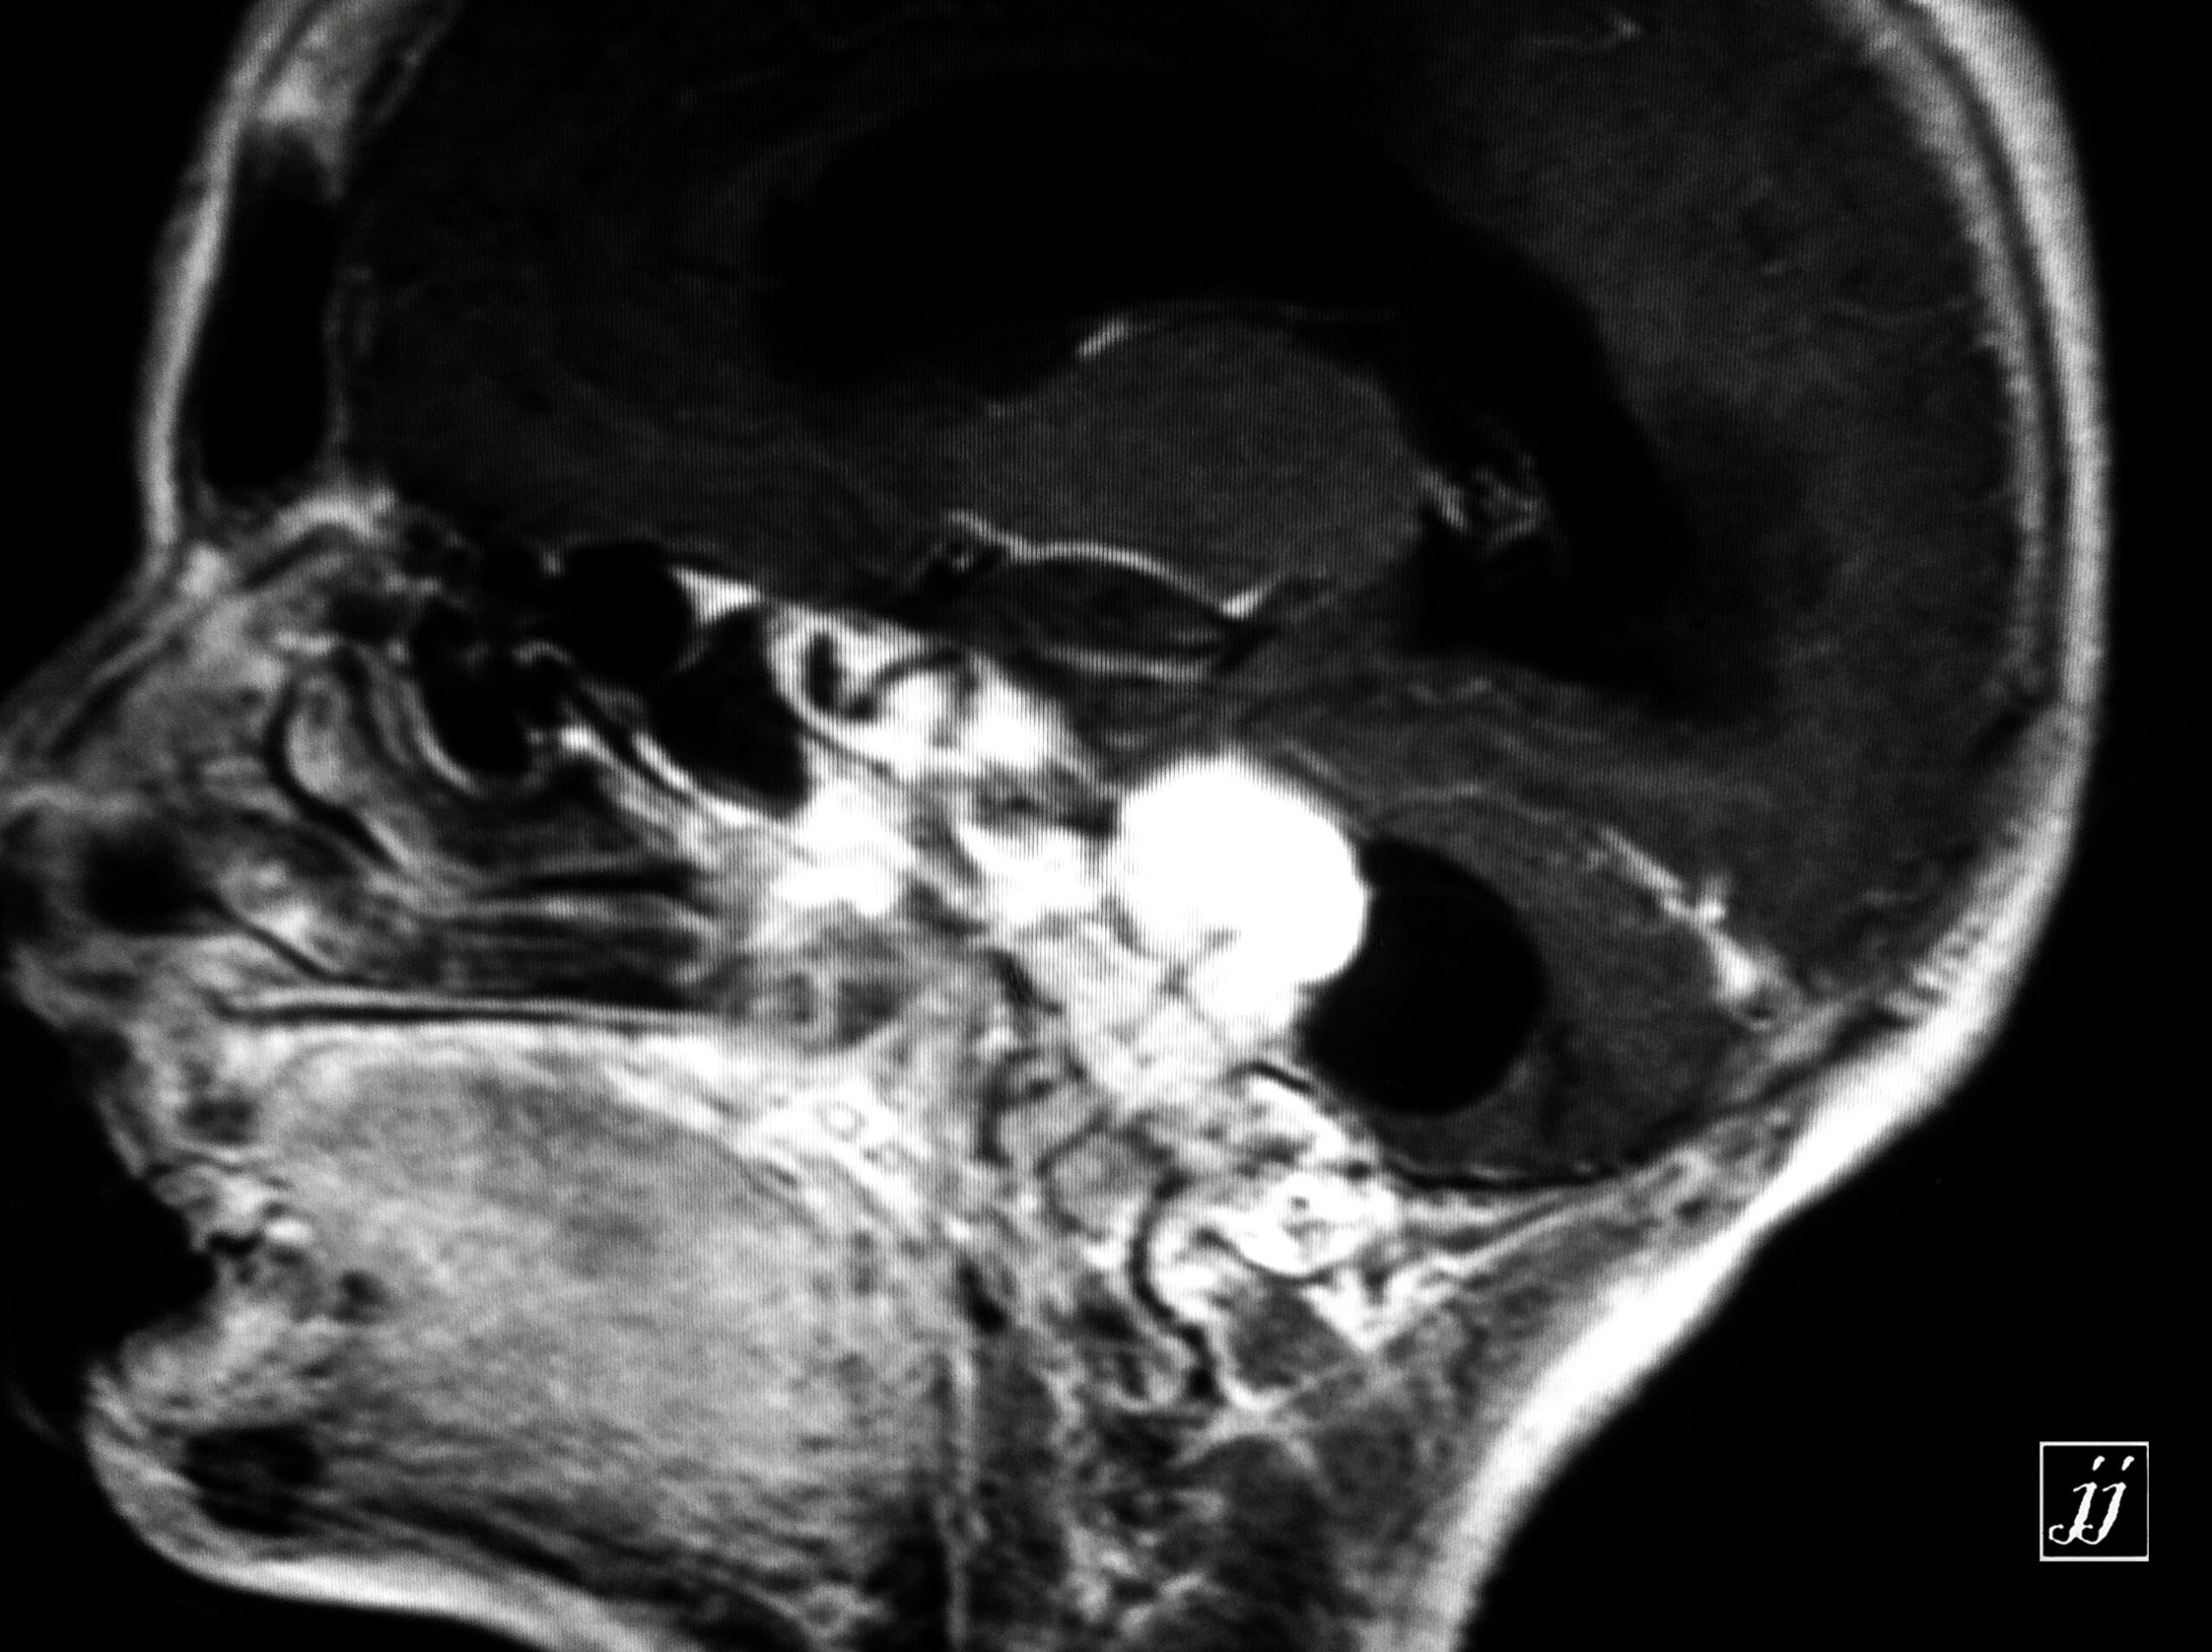

Brain- CPA tumor (2)